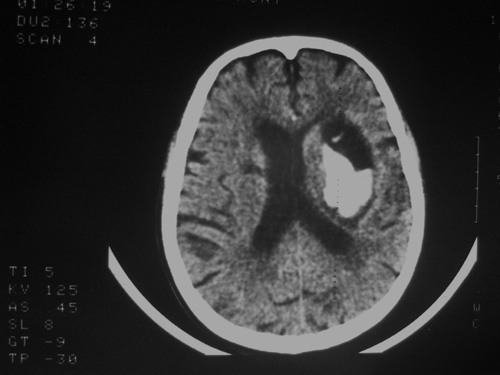

患者63岁,男。左侧肢体活动不灵一小时来诊。bp:175/75;家人否定有脑出血、脑梗死及其他病史。有嗜酒习惯。ct:右侧外囊区见不规则高密度影,边清,肯定是出血。可其周围低密度,边清,ct值与脑脊液相近,不像是水肿影,好似一软化灶形成。这种混合型病灶少见,请老师给予指导一下。

高密度灶为新鲜出血,临近低密度区为软化灶,可能为陈旧性梗塞或出血致。

软化灶出血,左侧脑室轻度受压。

软化灶内脑出血,且该软化灶应是既往出血所致.这样的病例也不少见.